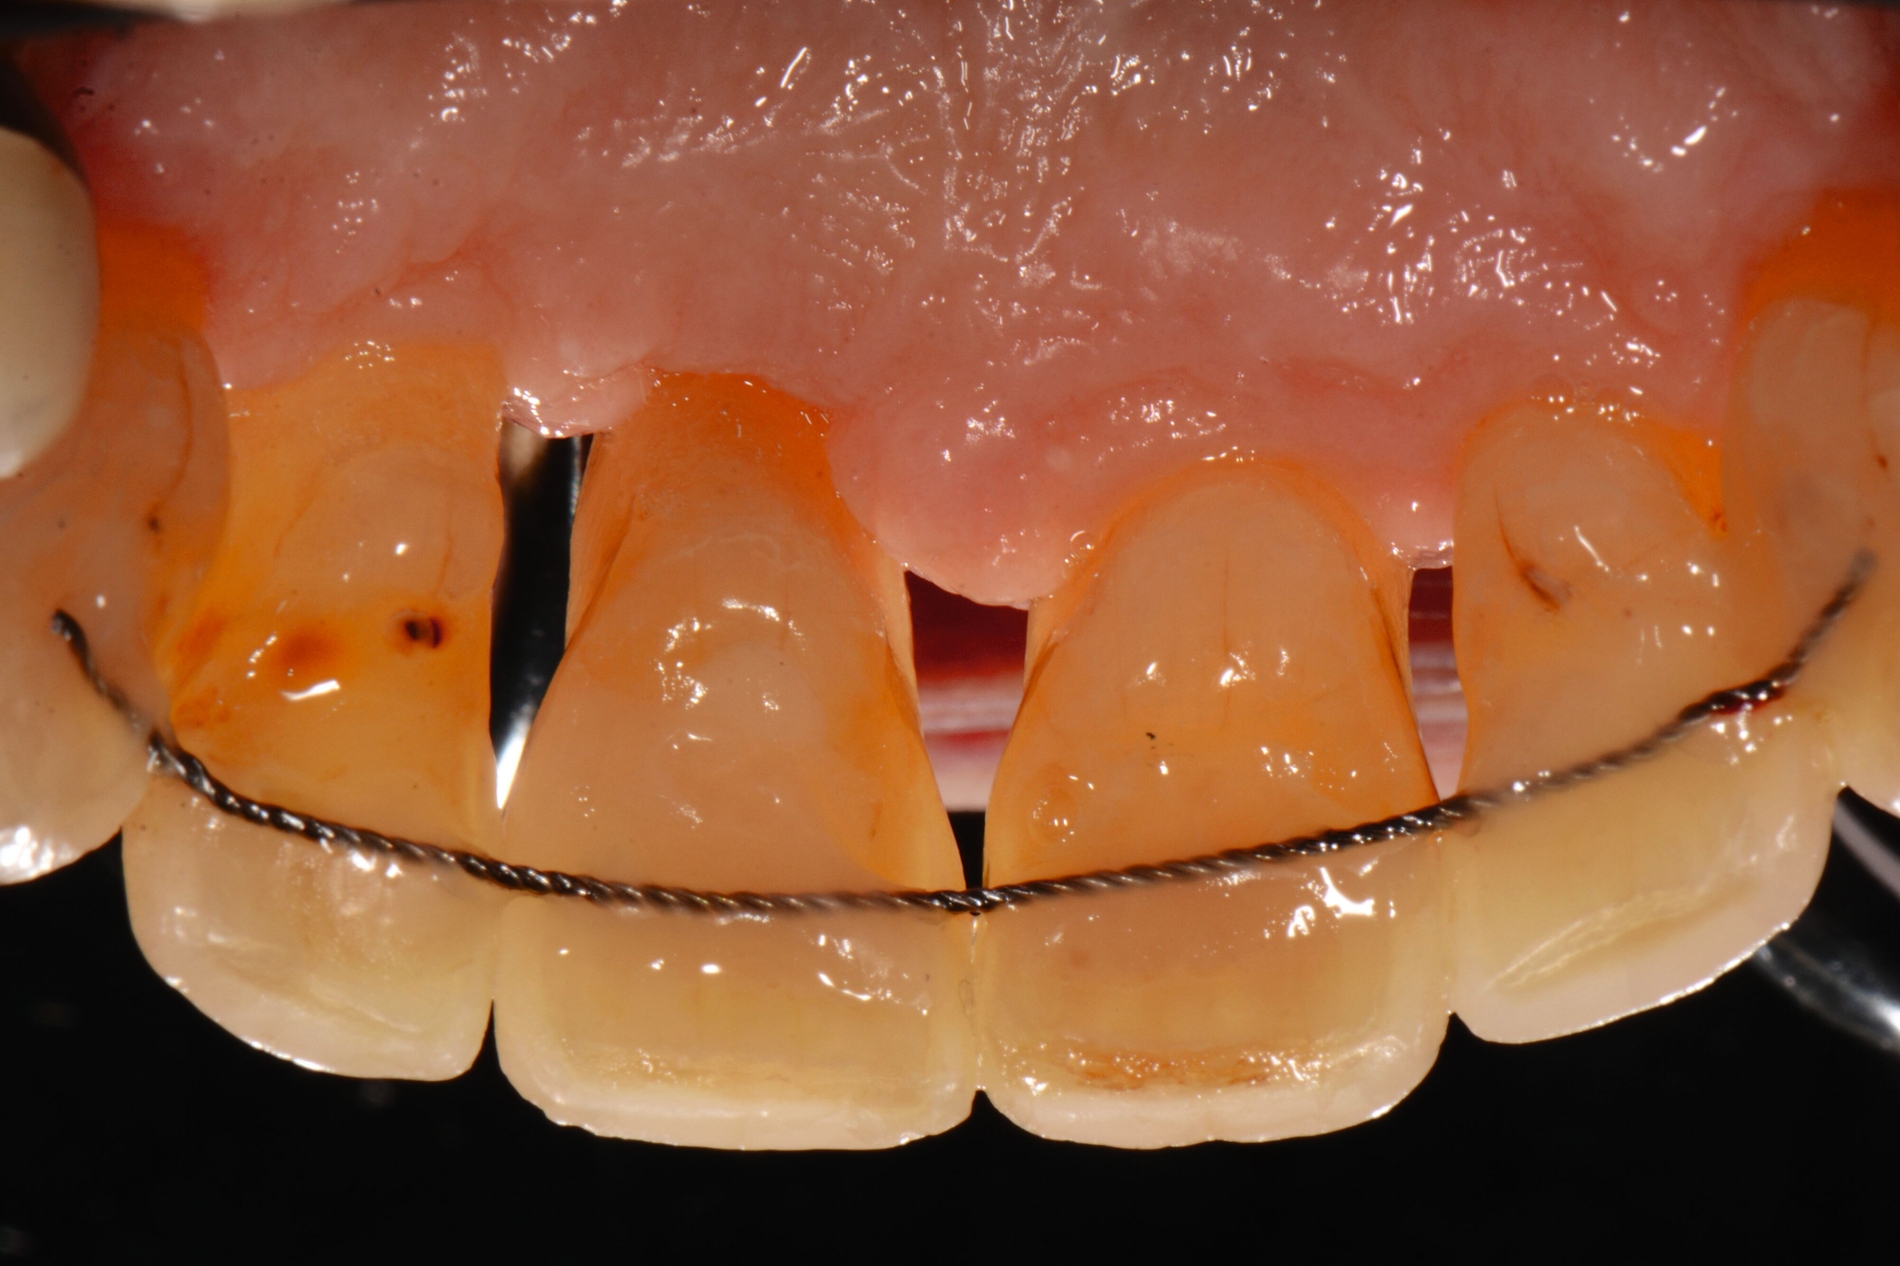

1. Kieferorthopädische Zahnbewegungen können entweder durch festsitzende (Zahnspangen) oder herausnehmbare (vom Patienten einsetzbare/entfernbare, beispielsweise herausnehmbare Platten oder thermoplastische Aligner) kieferorthopädische Geräte erfolgen. Eine nicht-randomisierte retrospektive Vergleichsstudie berichtete, dass festsitzende Apparaturen Vorteile gegenüber Alignern für PPD, aber nicht für RBL hatten (Abbildung 8). Allerdings wurde der Studie ein schwerwiegendes Risiko einer Verzerrung attestiert.

2. Die zirkumferentielle Fibrotomie der suprakrestalen Parodontalfasern wurde als zusätzliches chirurgisches Verfahren vorgeschlagen, um die Stabilität nach einer Korrektur stark gedrehter Zähne zu verbessern, oder als Eingriff zur Verbesserung des Attachmentniveaus während der kieferorthopädischen Intrusion. Der Einsatz der Fibrotomie als Ergänzung zur kombinierten Parodontal-/Kieferorthopädie-Behandlung war mit Vorteilen bei CAL und RBL, aber nicht bei PPD verbunden (Abbildung 9). Allerdings wiesen die beiden RCTs in mindestens zwei Bereichen ein hohes Verzerrungsrisiko auf.

3. Bei Parodontitis-Patienten im Stadium IV mit gesundem, aber reduziertem Parodontium kann die Verwendung von skelettalen Verankerungsvorrichtungen im Vergleich zu herkömmlichen Verankerungssystemen die Wirksamkeit der OT und deren Auswirkungen auf die parodontalen Ergebnisse verbessern (Abbildung 9). Aus Studien zu verschiedenen Verankerungssystemen ergaben sich keine Hinweise auf zusätzliche Vorteile für parodontale Parameter durch die Verwendung eines bestimmten Verankerungssystems während der kieferorthopädischen Therapie. Die Gesamtqualität der eingeschlossenen Studien wurde als „niedrig“ eingestuft.